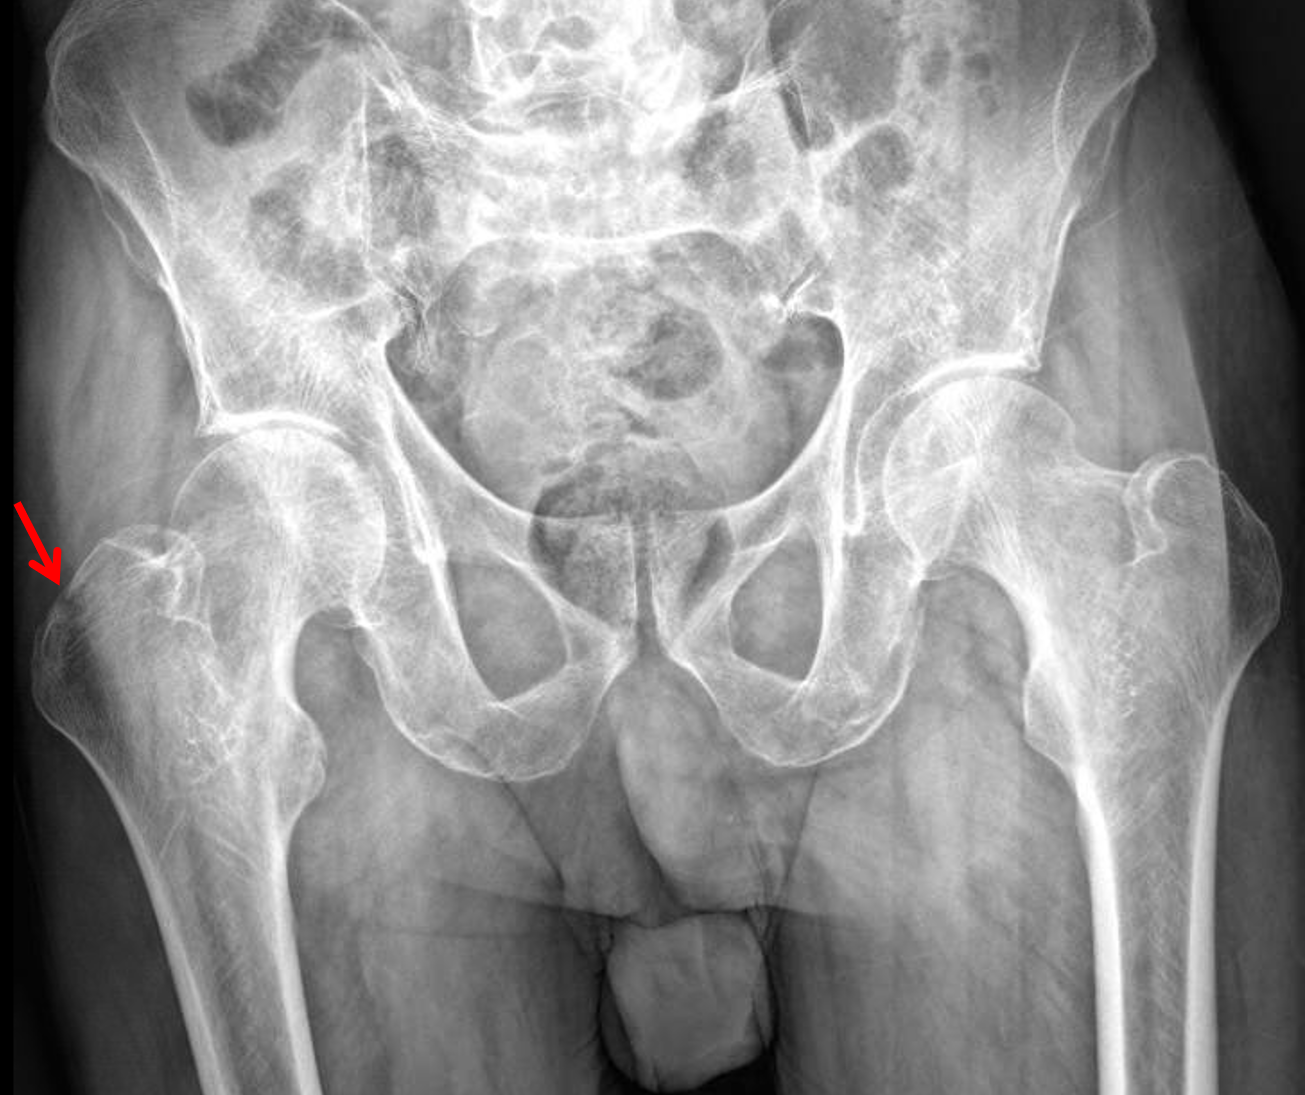

CaseStacks.com — Case #5 — Greater trochanter fracture

CaseStacks.com — Case #5 — Greater trochanter fracture from www.casestacks.com

Proximal femur fractures disclosures learning objectives organization anatomy imaging osteochondral subchondral femoral neck intertrochanteric greater troch. The greater trochanter of the femur is a large, irregular, quadrilateral eminence and a part of the skeletal system. Example of greater trochanter fracture. Articles show anterior deviation of the fragment. It is preferable for a number of reasons to use a long extramedullary device even though a limited open. Greater troch with <2.5cm displacement is protected weight bearing 3 months, if >2.5 cm then it risks. American academy of orthopaedic surgeons (orthoinfo.aaos.org): Greater trochanteric fractures generally result from forceful muscle contraction of a fixed limb, which usually occurs in those who are young and physically active. Related online courses on physioplus. Proximal femur fractures disclosures learning objectives organization anatomy imaging osteochondral subchondral femoral neck intertrochanteric greater troch. How these breaks differ and why recovery can be challenging these pictures of this page are about:right greater. Greater trochanteric pain syndrome (gtps) is a common cause of lateral hip pain, seen more commonly in females between the ages of 40 and 60. During implantation greater trochanter fracture occurred. Femoral greater trochanter avulsion fracture. Greater trochanter fracture anatomy • greater trochanter is the insertion site for hip abductors. It may occur due to direct injuries, especially in older adults, or it may occur indirectly due to string contraction of the gluteus minimus and gluteus medius. In all intertrochanteric fractures, if the fracture line extends distally, a long nail will be necessary.